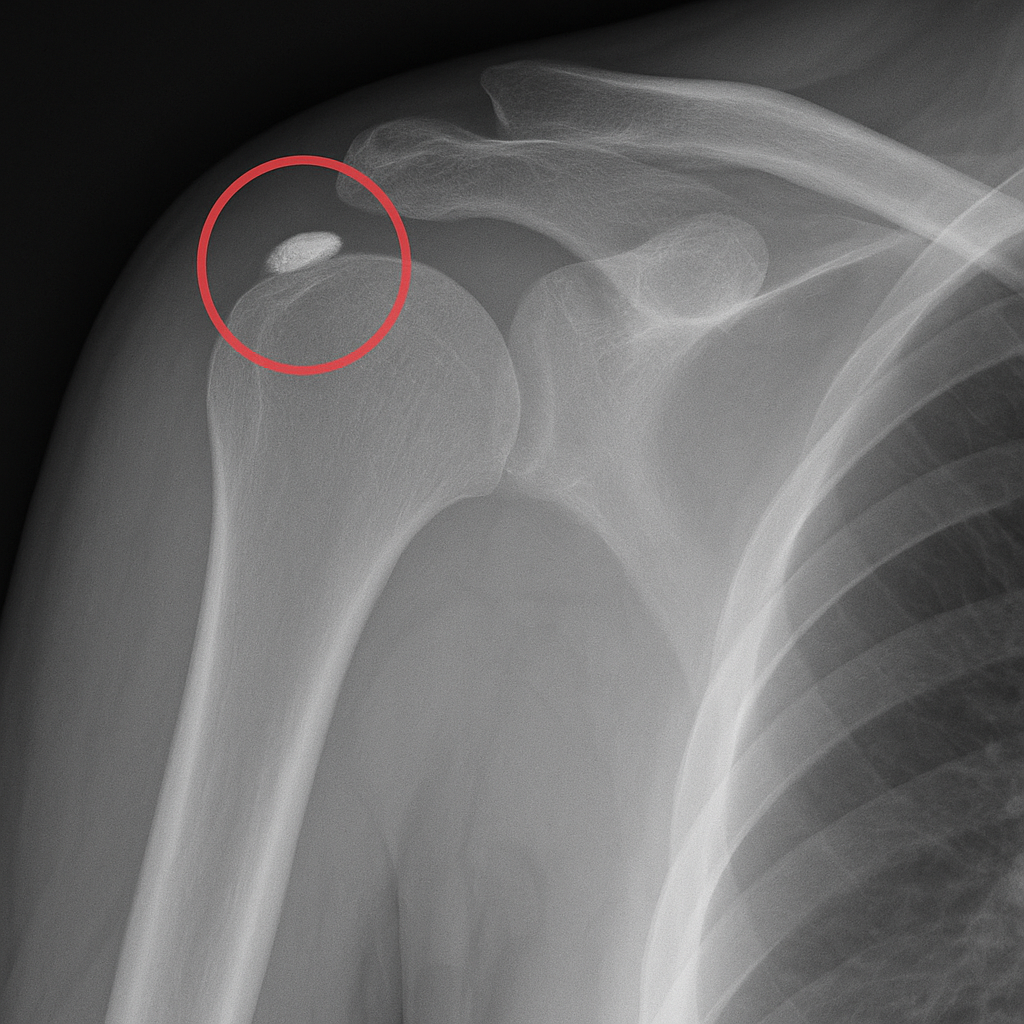

- Röntgen: a meszes góc jól látható.

A diagnózis felállítása legtöbbször nem okoz nehézséget, mivel a tendinitis calcificans jellegzetes képet mutat.